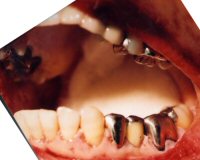

東京都大島町波浮港カキハラ磯 35-55 殺人被疑事件。ご遺体は荼毘にふされている。 警視庁大島警察署より送付された口腔内所見および口腔内写真のみを元に所見を記載したもの

Digital Dental Chart

写真および歯の番号をクリックすることで詳細な画像・情報を見ることができます。

陶材焼付冠 (Br支台)

残存歯

銀色インレー充填 (OD)

銀色全部被覆鋳造冠

修復物脱落の可能性 (OL)

銀色金属充填

埋伏or欠損

ポンティック (陶材)

陶材焼付冠 (Br支台)、歯冠色根面充填

銀色インレー充填 (MO)

銀色金属充填 (O)

処置歯 (治療中の可能性)

銀色インレー充填

銀色全部被覆鋳造冠 (Br支台)

ポンティック (レジン前装)

上顎左側犬歯については、冠にて修復後、唇側露出根面に歯冠色修復